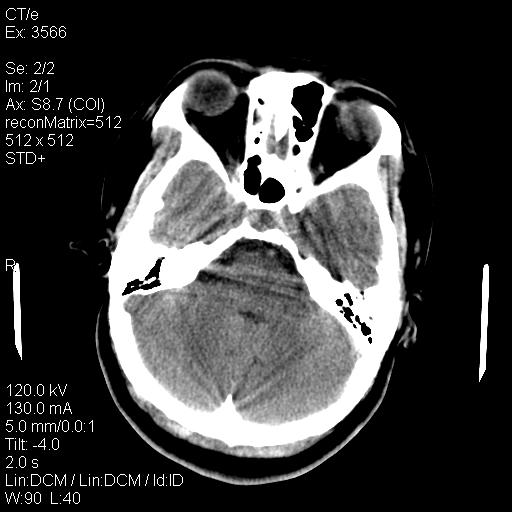

标题: CT9947:女,20岁,妊娠9个月,突然癫痫症状 [打印本页]

标题: CT9947:女,20岁,妊娠9个月,突然癫痫症状

双侧脑白质缺血缺氧性改变,并高度可疑“蛛网膜下腔出血”。

后可复性脑病,

考虑 妊娠子痫或妊高征

双侧脑白质缺血缺氧性改变.

考虑先兆子痫\\子痫致he,建议mri除外有无合并静脉窦血栓形成.

考虑pres

的确应该考虑可逆性后部脑病综合症--pres。感谢天南地北老师的指引,又学了一招儿,开心,呵呵!

考虑可逆性后部脑病综合症